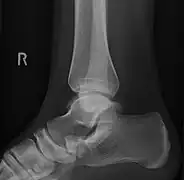

Lateral projection of type 2